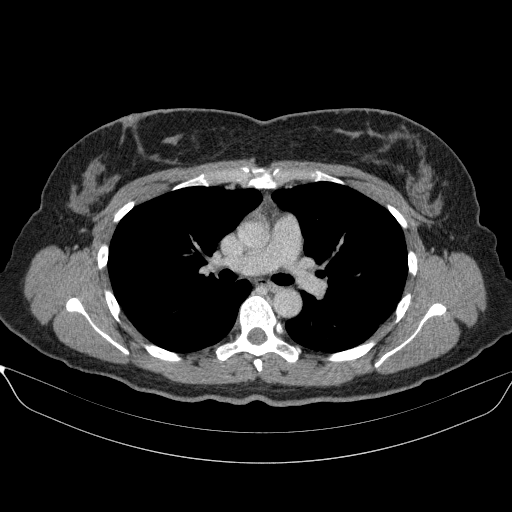

Original VENOUS CT scan

No window - Raw intensity values

Targeted Slice 70 - Mediastinum Window Analysis (Generated vs Real Venous)

0.631

Mediastinum SSIM

67.6

Mediastinum RMSE

33.3

Mediastinum MAE

Average Mediastinum Window Metrics Across All Slices (170 slices) - Generated vs Real Venous

0.621

Mediastinum SSIM (Avg)

73.2

Mediastinum RMSE (Avg)

37.1

Mediastinum MAE (Avg)